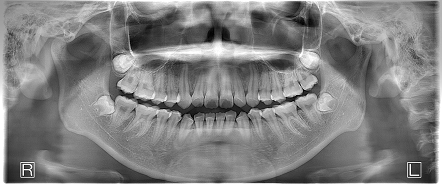

お口の中全体の写真

Before

After

- 患者の症状

- 上下の前歯が歯並びガタツキが気になるということで矯正治療の相談をされた方です。

- 治療結果

- 上下とも歯列のガタツキは改善されました。